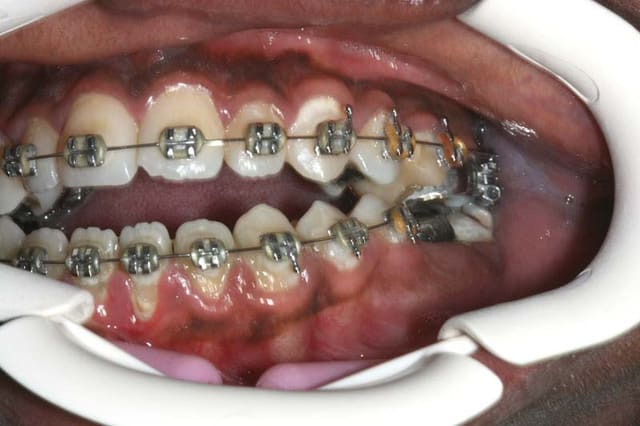

et encore, je vous ai pas montré le transpalatin qui rentre dans le palais

par contre, les caries et l'absence de motivation de brossage sont clairement visible

je crois que tu dois commencer par traiter ton sens transversal bjc sur la foto de face on voit bien un défaut de largeur maxillaire et une déviation mandibulaire.